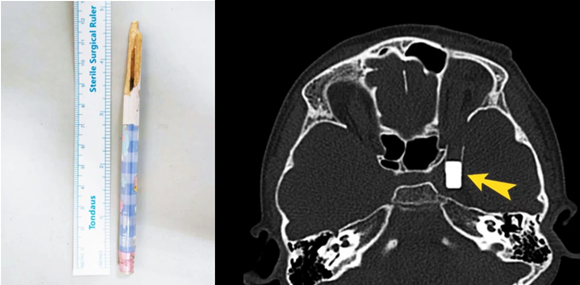

左图:患者自行拔出的铅笔残端;右图:术前评估异物位置

经过眼科、介入血管外科、儿科、麻醉科等初步评估,小古丽的伤情渐渐明晰起来:铅笔木制主体已经自行拔出,异物位于中颅窝底部临近海绵窦的部位,最尾端位于眶上裂的后方。幸运的是,橡皮头没有戳破大动脉。眼眶内仅有微小残端保留一线手术机会。